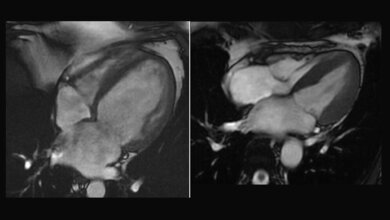

Das Hamburger Duo hat mit seiner Arbeit gezeigt, wie eine individualisierte Therapie bei genetischen Herzerkrankungen ermittelt werden kann. Über 160.000 Menschen leiden in Deutschland an der HCM. Damit handelt es sich um die häufigste erbliche Herzerkrankung. Hauptmerkmal ist eine verdickte Wand der linken Herzkammer. Im Laufe der Erkrankung kann die HCM zu Luftnot und Herzrhythmusstörungen führen, schlimmstenfalls sogar zum plötzlichen Herztod. „Nur mit Hilfe wirkungsvoller Behandlungsmethoden lassen sich die bedrohlichen Folgen der HCM verhindern. Passgenaue Therapieansätze zur gezielten Bekämpfung der HCM sind daher dringend notwendig“, betont Prof. Dr. med. Dietrich Andresen, Vorstandsvorsitzender der Deutschen Herzstiftung. „Mit ihrer prämierten Arbeit sind die beiden Forscher den Ursachen der HCM auf die Spur gekommen – eine vielversprechende Basis für neue Behandlungsstrategien gegen die HCM.“

Um die Funktion dieses Gendefekts besser charakterisieren zu können, stellten die Wissenschaftler aus Millionen dieser Herzzellen ein künstliches Herzgewebe her. „Es kontrahiert wie ein richtiges Herz und zieht sich auf elektrische Reize hin zusammen“, sagt Dr. Prondzynski. Ein Zentimeter lang und ein, zwei Millimeter dick war das an HCM erkrankte Laborherz der Forscher, das an Silikonstreifen befestigt in Zellflüssigkeit hing. Um die kranken Herzzellen mit einer gesunden Kontrolle vergleichen zu können, korrigierten die Forscher mithilfe der Genschere (CRISPR/CAS9) die Mutation in den Stammzellen. „So hatten wir gesunde Ausgangszellen, wie von einem gesunden Zwilling“, erklärt Dr. Prondzynski. So entstanden ein krankes und ein gesundes Laborherz für ihre Untersuchungen.

Das Ergebnis: Die Kontraktionen der kranken Herzzellen waren stärker und dauerten länger als bei den gesunden. Die elektrische Erregung war deutlich in die Länge gezogen. Als zugrunde liegenden Mechanismus vermuten die Wissenschaftler, dass der winzig kleine neu erkannte Gendefekt bewirkt, dass das für die Zellstruktur verantwortliche Protein fehlerhaft ist und seine Funktion nicht richtig ausüben kann. Das hat dann wiederum zur Folge, dass vermehrt Kalziumionen in die Herzzellen einströmen und die elektrische Erregungsleitung und Kontraktionszeit verlängern. Damit erhöht sich die Gefahr für Extraschläge. „Dies könnte ein Grund für Herzrhythmusstörungen bei HCM-Betroffenen sein“, so Dr. Lemoine.